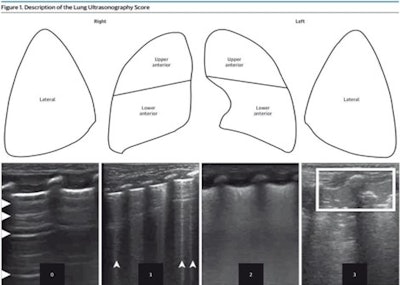

1Each lung has been split into three parts. Each area has been given a score between 0 and 3. Score values are shown in Ultrasonograms to match 4 different patterns. During a longitudinal scan with a high-resolution linear probe, pictures of patterns were taken. The scores are as follows: 0 means A pattern, 1 means B pattern, 2 means severe B pattern, and 3 means extended consolidation. Images available for publishing under a creative commons license, CC BY-NC-ND 4.0.